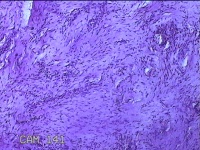

舌头肿物

性别

女

年龄

25岁

临床诊断

一般病史

无

标本名称

大体所见

灰白粉红色肿物0.7x0.5x0.2cm一个,表面光滑。

纤维性息肉